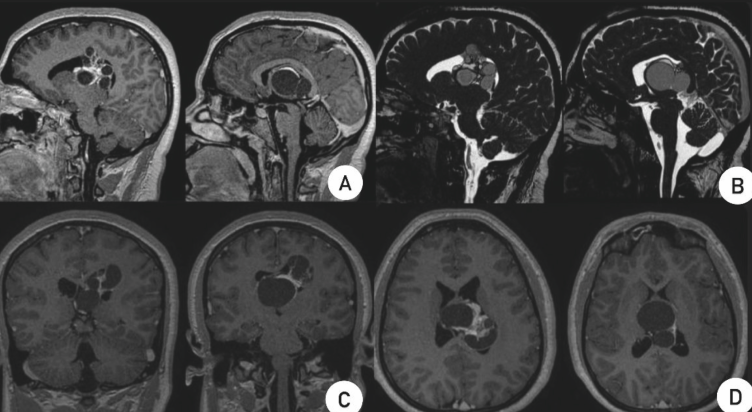

MATURE INTRACRANIAL TERATOMA: CASE REPORT

Intracranial terato- mas are rare germ cell tumors, accounting for approximately 0.5% of all intracranial tumors. They can be classified as mature, immature, or malignant, and are typically located along the midline of the brain, particularly around the third ventricle, pineal region, and suprasellar area.

Case Report: A 20-year-old female pa- tient presented with a history of seizures, hea- dache, nausea, vomiting, and diplopia. A cra- nial MRI revealed a multicystic lesion in the left lateral ventricle with ventricular dilation. Surgery was performed with an interhemis- pheric approach and partial resection of the lesion, confirming the diagnosis of a mature teratoma. The patient had a favorable recovery with no neurological deficits.